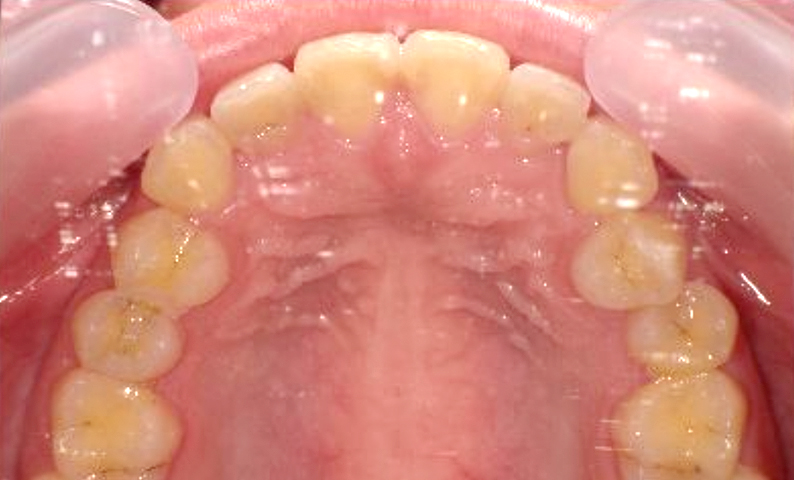

症例_001 前歯「捻転歯」症例

治療期間:6ヶ月金額:48万円+税20代女性少しのねじれ捻転歯下の八重歯

| Before | After |

|---|---|

|